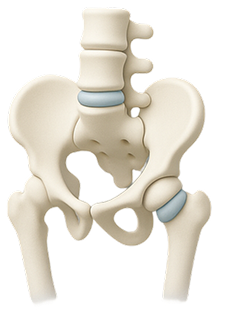

When the soft center of a spinal disc pushes through a crack in the exterior, it can press on nerves and cause pain.

Lower back pain can stem from several underlying issues, including: